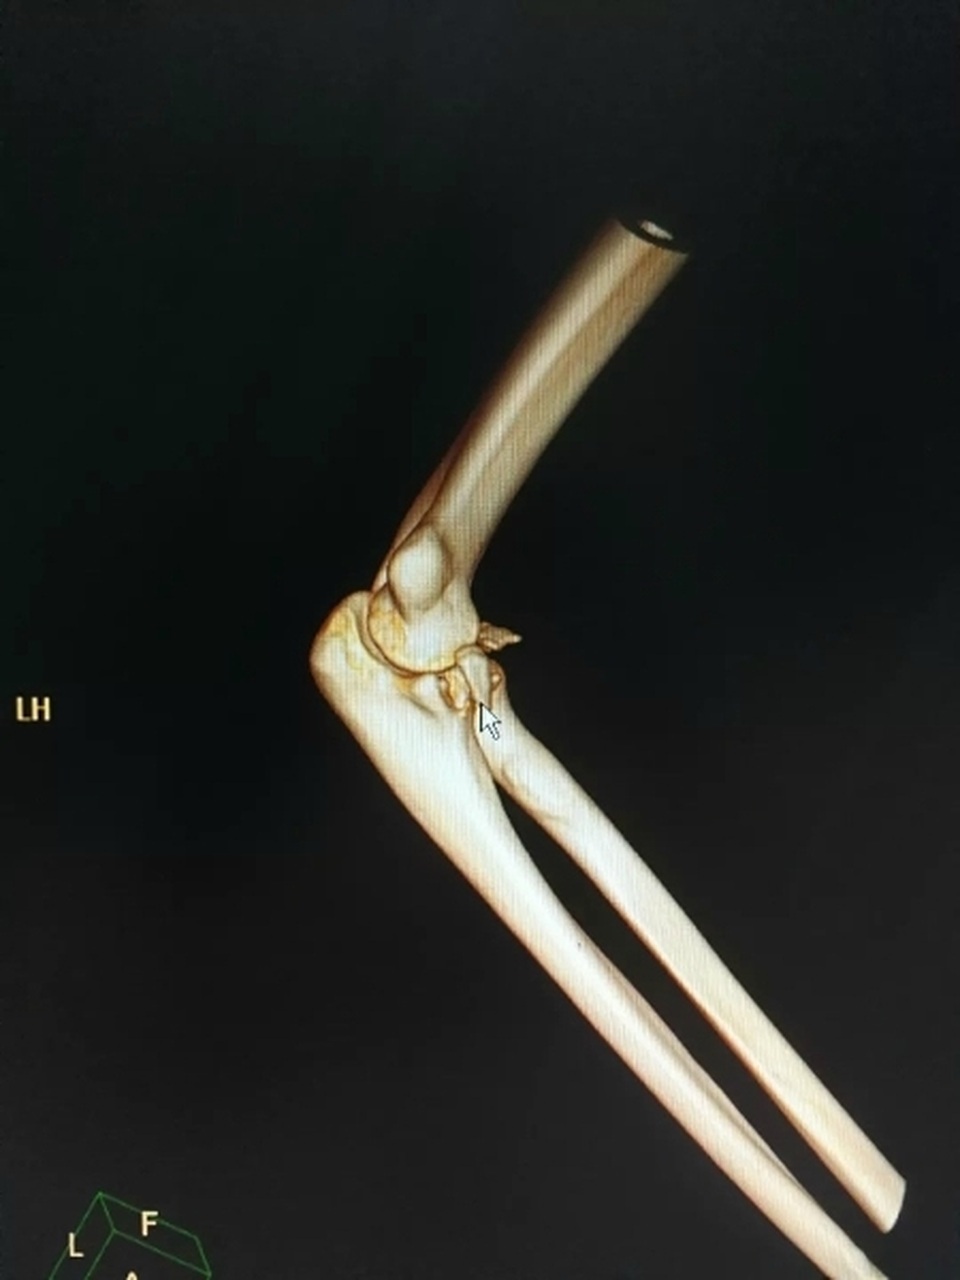

Ngay sau đó, cánh tay anh ta đau dữ dội khiến hai người phải vội vàng đến khám tại một bệnh viện gần nơi xảy ra vụ việc. Chụp CT cho thấy cử chỉ lãng mạn đã làm gãy xương cánh tay của chàng trai và khuỷu tay của anh ta cũng bị trật khớp.